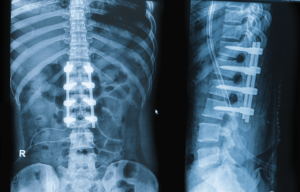

Complex paediatric deformity correction surgeries address severe spinal conditions in...

Corpectomy and vertebral osteotomy are advanced spinal surgeries used to...